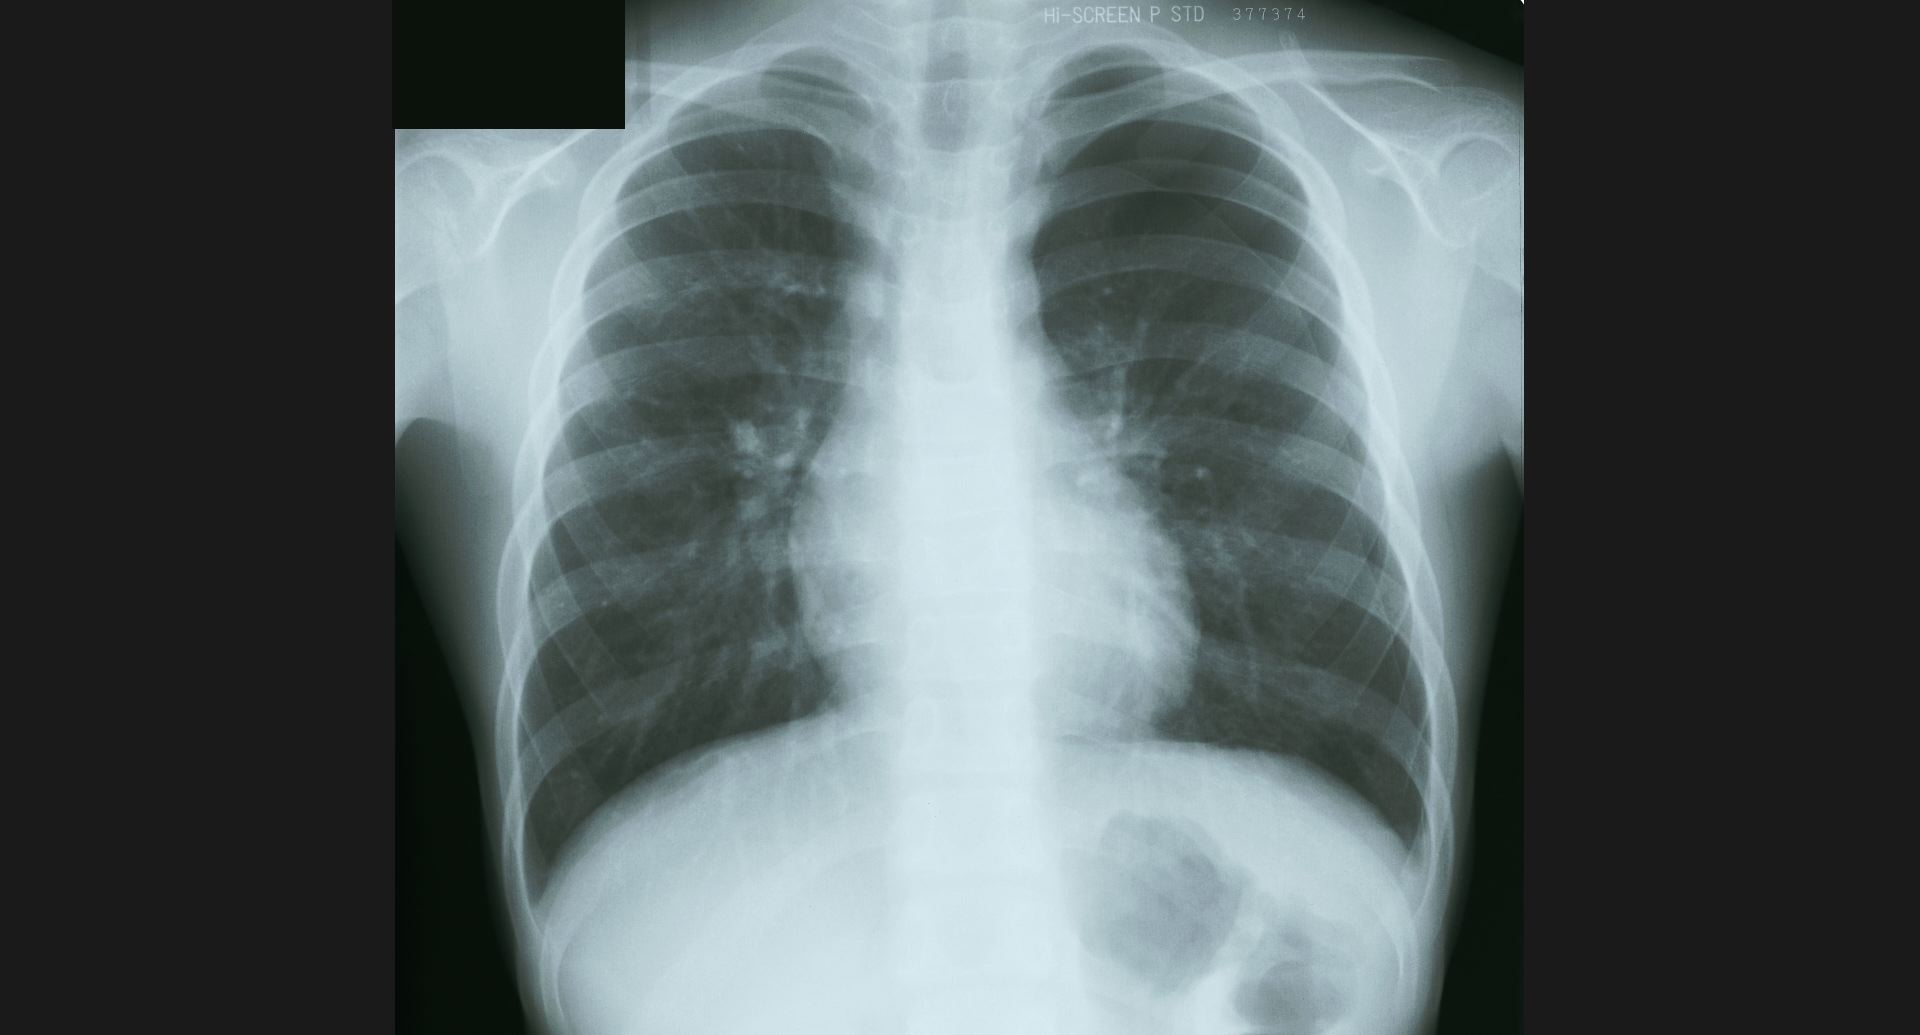

fig.5(93KB) :Post-plomboge chest

ピンポン玉、左肺上葉の細かい石灰巣。